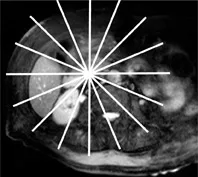

Figure 4. Acquisition 2D de multiples coupes épaisses, selon une distribution radiaire en restant centré sur le bas cholédoque (A).

L’acquisition (B) montre une dilatation de la VBP avec un arrêt cupuliforme au niveau du bas cholédoque (tête de flèche).

On suspecte une lithiase, mais sans pouvoir éliminer une image de pseudo- calcul liée à une contraction du sphincter.

L’acquisition radiaire suivante (C), lors d’une ouverture sphinctérienne, établit formellement le diagnostic, en montrant le passage de bile autour d’un calcul enclavé du bas cholédoque (tête de flèche).